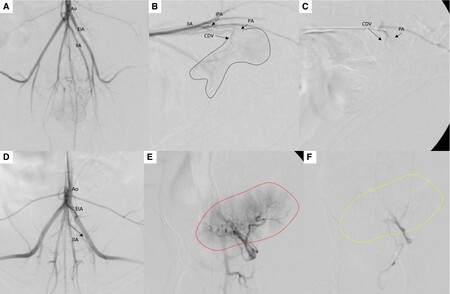

■ 방광 종양으로 인한 빈혈 환자에 ‘방광 종양 색전술’ 성공

첫 번째 논문은 거대 방광 종양으로 지속적인 혈뇨와 빈혈을 보인 개 2마리에서 종양 색전술을 적용한 사례로 'Journal of Small Animal Practice(SCI)'에 게재됐다.

전통적으로 비뇨기 종양 색전술은 합병증 위험으로 전립선 종양에만 국한됐지만 본 증례는 종양으로 공급되는 혈관만을 초선택(superselective) 했고, 시간이 지나 재개통이 되는 색전 물질(gelatin sponge particle)을 이용해 효과를 극대화 하면서도 심각한 합병증이 발생하지 않도록 하였다.

시술 직후 혈뇨는 즉시 개선됐으며, 배뇨곤란 증상도 완화됐다. 또한 종양 크기는 50% 이상 감소했으며, 빈혈과 혈소판 감소증을 보였던 환자에서도 4주만에 혈액 수치가 정상화 되었다.

해마루 인터벤션센터는 현재까지 하부 비뇨기 종양 색전술을 200례 이상 시행했으며, 30여 마리를 장기 추적한 전향적 연구도 유명 SCI 저널 게재를 앞두고 있다.